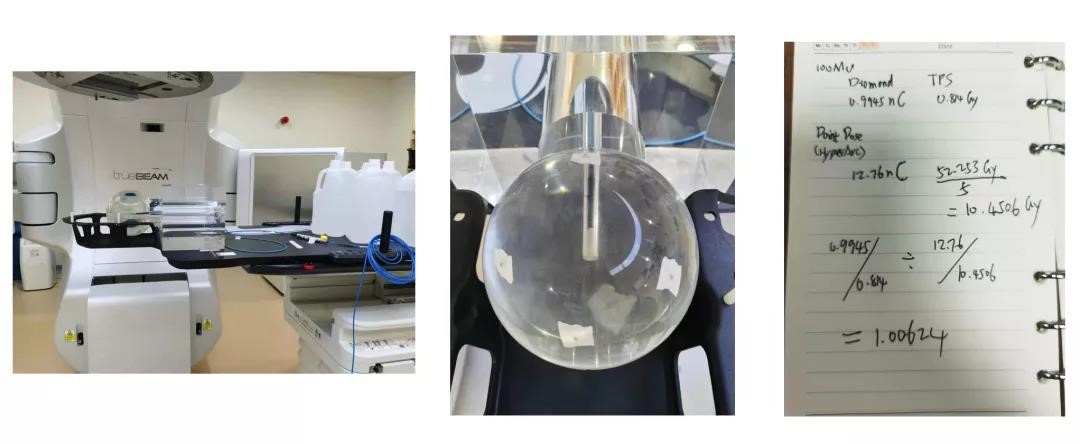

4、剂量验证

使用钻石探头和头部仿真模体进行点剂量验证